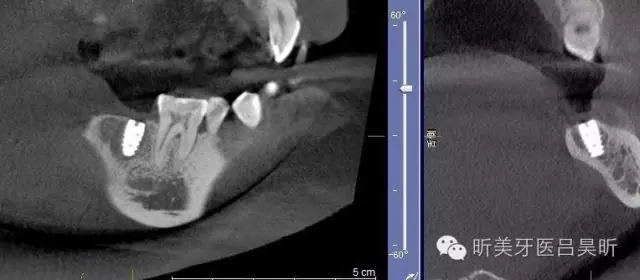

術(shù)前CBCT截圖,垂直骨量似乎感覺(jué)良好

可見(jiàn)種植位點(diǎn)舌側(cè)區(qū)凹陷,牙槽骨上部舌傾明顯。

術(shù)后CBCT 檢查,植入位點(diǎn)良好,與術(shù)前設(shè)計(jì)基本一致,并實(shí)現(xiàn)安全植入。